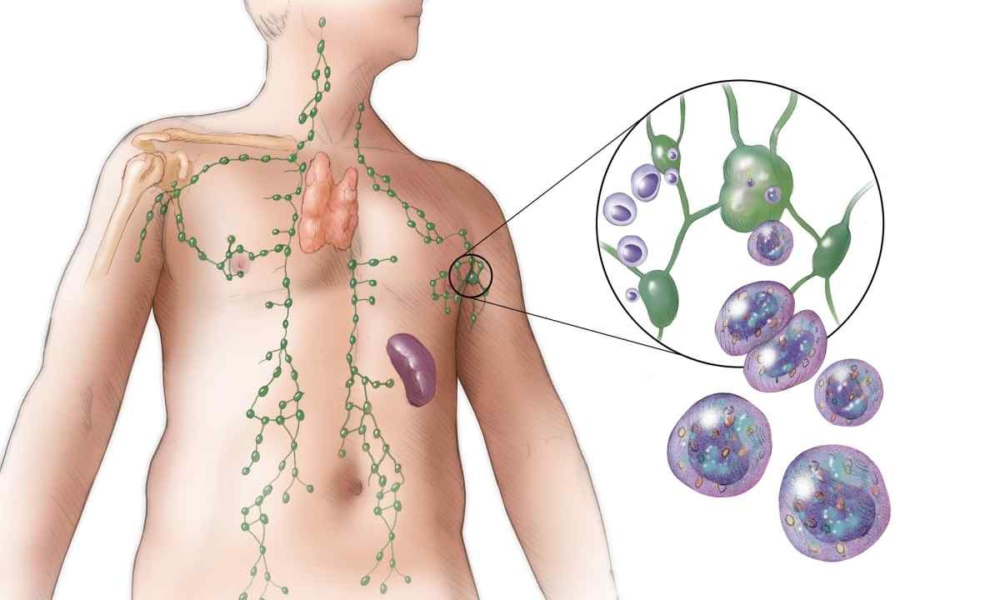

За складом лімфа схожа на плазму крові, але без еритроцитів. Зате в ній багато лейкоцитів – клітин імунної системи. І це не випадково. Лімфа тісно пов’язана з імунітетом, захистом від інфекцій і виведенням усього зайвого.

По-перше, очисна функція. Лімфа збирає з тканин продукти обміну, токсини, залишки зруйнованих клітин. Усе це транспортується до лімфатичних вузлів, де фільтрується. Якщо уявити організм як місто, то лімфа – це система прибирання сміття.

По-друге, захисна функція. Лімфатичні вузли – це своєрідні блокпости. Тут знешкоджуються бактерії, віруси, чужорідні частинки. Саме тому під час інфекцій лімфовузли збільшуються й стають болючими – система працює на максимум.

Де знаходиться лімфа у людини?

По-перше, лімфа циркулює в лімфатичних судинах. Вони схожі на кровоносні, тільки тонші. Ці судини проходять практично по всьому тілу – у руках, ногах, шиї, грудях, животі. Саме по них лімфа повільно рухається від тканин до лімфатичних вузлів, а згодом повертається в кровообіг.

По-друге, лімфа накопичується й фільтрується в лімфатичних вузлах. Це ті самі “горошини”, які можна намацати на шиї, під пахвами або в паху. Вузли є:

Там лімфа очищується від бактерій, вірусів і токсинів.